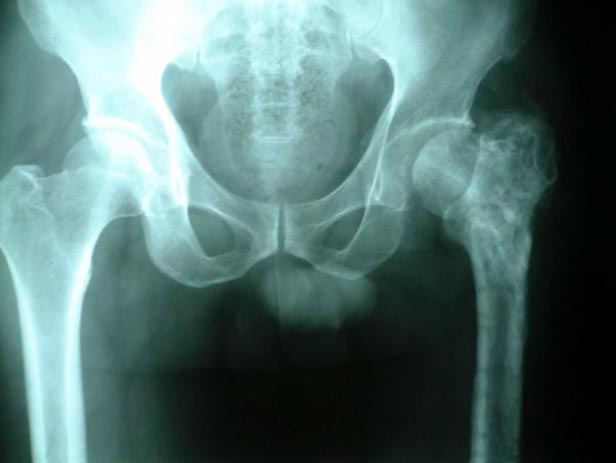

• 关节破坏的X线改变

关节软骨破坏,关节间隙消失               股骨颈骨折,容易发生不愈合